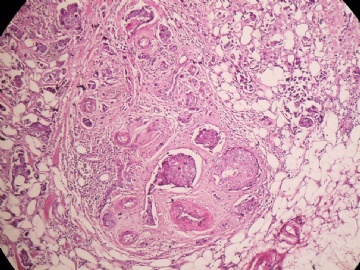

B2778浸润性导管癌?

姓    名: ××× 性别:  女 年龄:  45

标本名称:  左侧近乳晕处肿物

简要病史:  患者描述有疼痛

肉眼检查:  肿物一个2.5*2*1厘米,切面灰白质地硬。

• 浸润性导管癌?图1

• 浸润性导管癌?图3

图3

上皮样细胞,大部分粘附成团成巢,明显浸润。大部分细胞大,核级别高,少数图中见松散的小细胞。未见原位癌。

大细胞考虑浸润性导管癌(3级),小细胞要排除小叶癌。如果有条件请做免疫组化。

乳晕处好像有个乳头腺病

图像也是很可怕

怎么鉴别呢